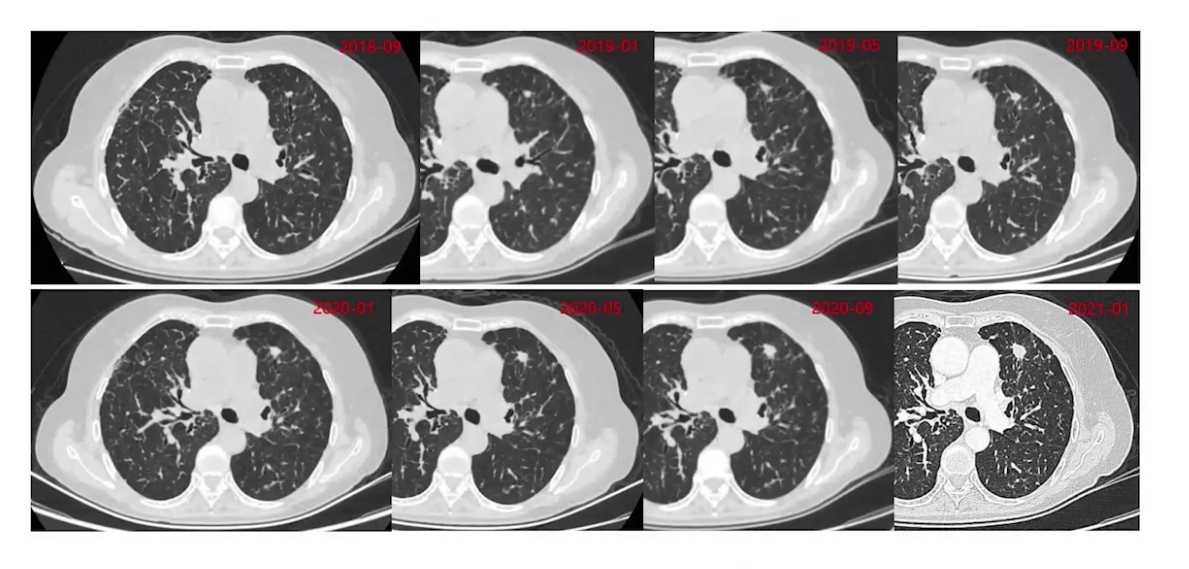

2018年9月发现左肺上叶新增结节并逐渐增大,2021年1月全身评估后,考虑患者处于寡进展状态,2月行胸腔镜下左肺上叶楔形切除术,切除增大结节。术后病理提示肺组织中可见中低分化腺癌,浸润肿瘤最大径1.2cm,送检NGS检测提示EGFR exon19缺失突变、EGFR exon20的T790M突变及MET基因扩增。术后继续奥西替尼靶向治疗。

6、联合靶向治疗

2022年5月开始左肺结节逐渐增大,2023年7月复查时结节明显增大,PET-CT检查全身评估后,经多学科讨论,因既往NGS检测提示MET扩增,考虑口服塞沃替尼靶向治疗后复查再评估是否放疗,8月开始奥西替尼联合塞沃替尼治疗,1个月后胸部CT复查,左肺增大的结节明显缩小。因治疗药物有明显消化道不良反应,9月改用氟美替尼联合塞沃替尼治疗,患者目前维持治疗,一般情况良好。